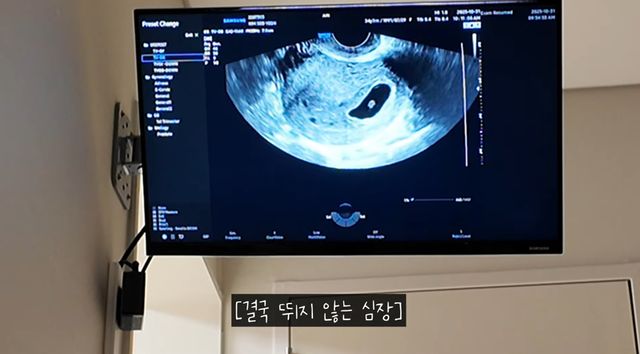

의사는 "정상적으로 임신이 진행될 가능성은 1~2% 미만일 것 같다. 하지만 기다려 봐야겠죠? 괜히 희망 고문만 하다가 마는 경우가 워낙 많아서 일반적인 코스에서는 진행되긴 어렵다고 봐야한다. 심장 소리는 안 들리는데 깜빡거리는 게 보인다"라고 진단했다.

두 사람은 상의 끝에 3일 더 기다려보기로 했다. 3일 뒤에 다시 검사했지만 배아의 심장은 뛰지 않았다. 의사는 "다음 임신을 위해서"라며 "이런 걸 계류유산이라고 한다. 계류유산이라는 의미는 유산이 됐는데 남아있다는 뜻이다. 만들어지고 있었는데 문제가 생겨 진행이 안 되는 상황이다. 보통 7~10% 안쪽에서 늘상 발생한다"라고 설명했다.